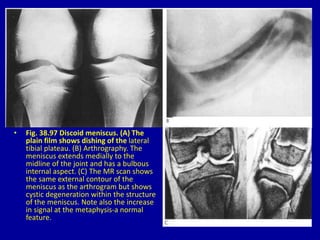

• Fig. 38.97 Discoid meniscus. (A) The

plain film shows dishing of the lateral

tibial plateau. (B) Arthrography. The

meniscus extends medially to the

midline of the joint and has a bulbous

internal aspect. (C) The MR scan shows

the same external contour of the

meniscus as the arthrogram but shows

cystic degeneration within the structure

of the meniscus. Note also the increase

in signal at the metaphysis-a normal

feature.

• Fig. 38.97Discoid meniscus. (A) The plain film shows dishing of the lateral tibial plateau. (B) Arthrography. The meniscus extends medially to the midline of the joint and has a bulbous internal aspect. (C) The MR scan shows the same external contour of the meniscus as the arthrogram but shows cystic degeneration within the structure of the meniscus. Note also the increase in signal at the metaphysis-a normal feature.